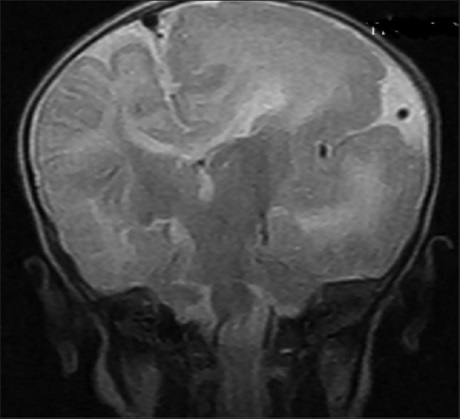

Vertebrobasilar Dolichoectasia

Dr. Eswaradass Prasanna Venkatesan, Ramasamy Balakrishnan, Kalidoss Ramadoss, G. Gnanashanmugham (Author)

93-95